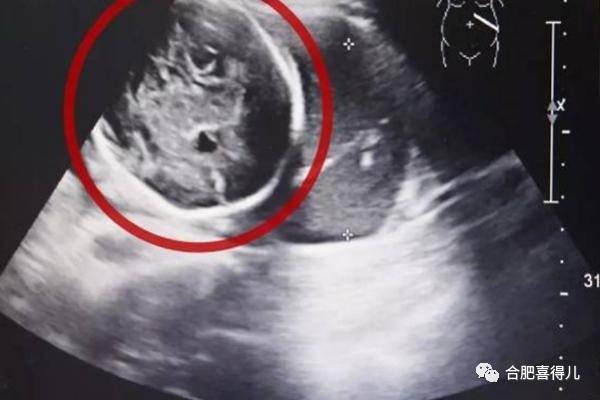

经B超检查,小芳竟然已经怀孕了,而且胎儿已经长到了6个多月!但是让人震惊的是胎儿并没有长在子宫里,而是长在了腹腔内。经过确诊,小芳为“腹腔妊娠”,是宫外孕的一种,这种发病率约为1:15000,母体死亡率约为5%,胎儿存活率仅为1%的罕见妊娠!

对此,合肥喜得儿孕育医院专家表示,小芳这种“腹腔妊娠”的情况确实很罕见。胎盘附着的位置不同,腹腔妊娠的危险性也不同,如果是附着在肝脏、脾脏等实质性脏器上则危险性较大。